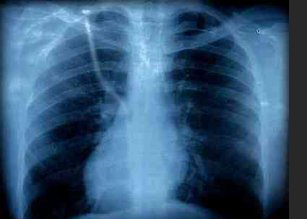

胸部影像学检查

不同类型肺结核的典型胸部影像学表现如下: 原发性肺结核表现为原发病灶及胸内淋巴结肿大或单纯胸内淋巴结肿大。 急性血行播散性肺结核表现为两肺广泛均匀分布的,大小、密度一致的粟粒状阴影;亚急性或慢性者病变以上…